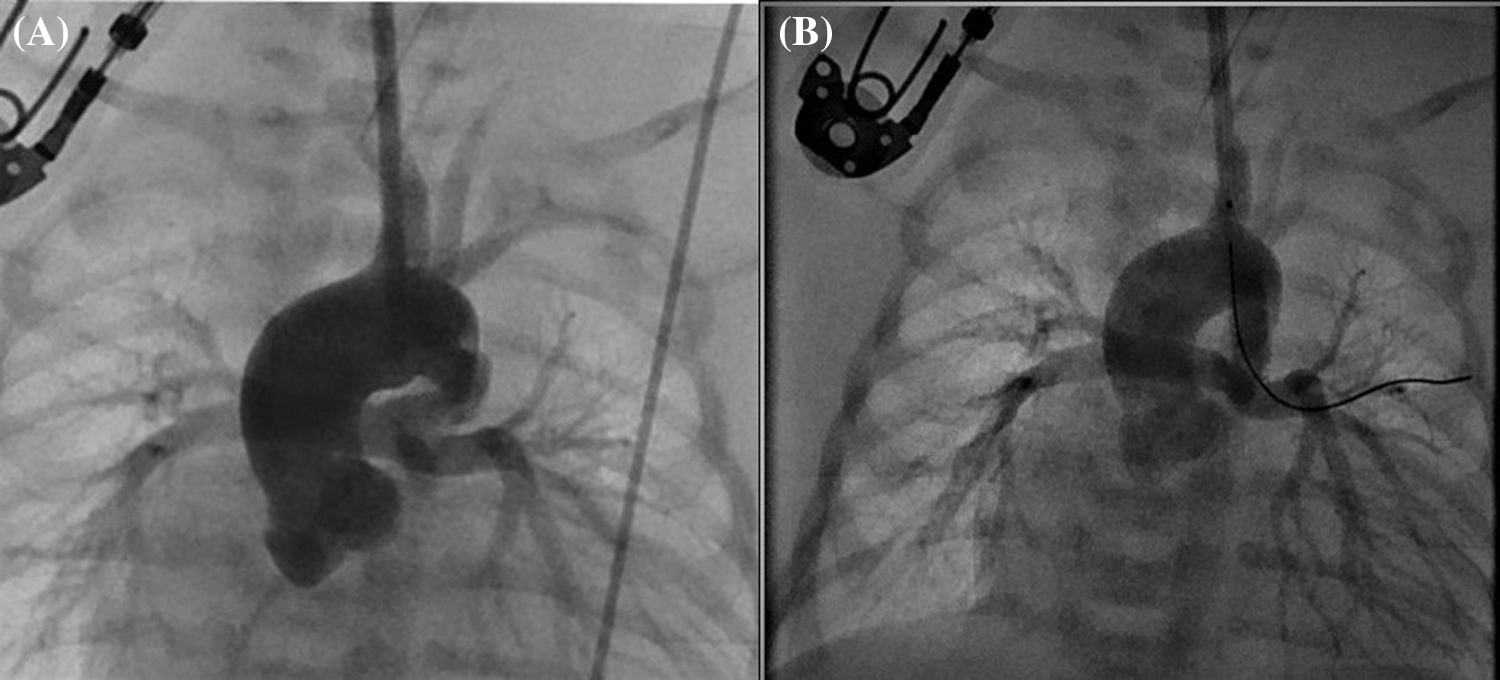

Although CC was performed more frequently in patients with ventricular septal defect + pulmonary atresia and stent/mBT shunt stenosis, femoral puncture was used more frequently in patients with intact ventricular septum + pulmonary atresia (p = 0.008). Angiographic images of a patient with intact ventricular septum + pulmonary atresia who underwent ductal stenting via CC are shown in Fig. 4. In the comparison made according to the diagnostic groups, there was no difference in the duration of the procedure between the femoral and CC groups in patients who underwent the diagnostic procedure. In patients diagnosed with ductal stent, balloon aortic valvuloplasty and balloon coarctation angioplasty, the procedure times were found to be significantly lower in the CC group compared to the femoral group (Table 2).

Figure 4: (A) Angiographic image obtained before the placement of a ductal stent for a vertical and tortuous ductus arteriosus, with contrast administered through the sheath placed with carotid cut-down, in a patient with pulmonary atresia and intact ventricular septum. (B) Angiographic image of the same patient after ductal stent placement